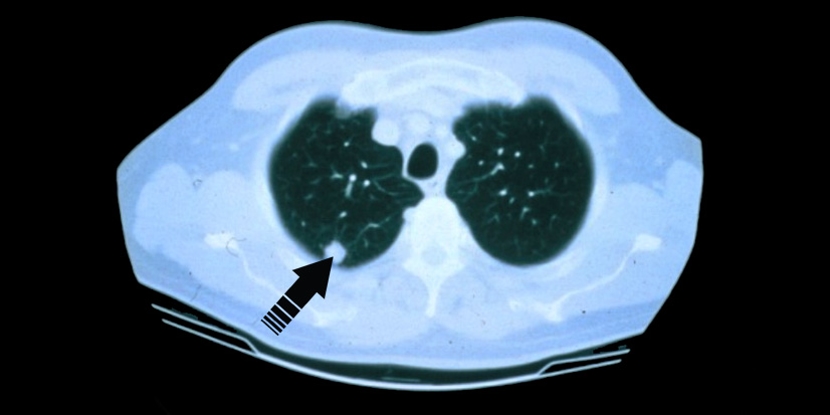

A low dose CT scan aids in finding cancer sooner and with early detection generally, more treatment options may be available.

Now more than ever, advanced screening can detect lung cancers earlier, so individuals can have more treatment options and get better outcomes. The screening utilizes a “low-dose” CT scan to find any nodules especially in people who do not yet show any signs of lung cancer but may be considered high risk for the disease. Remember, the screening is a process, not a single test. An individual must adhere to the screening for early detection.